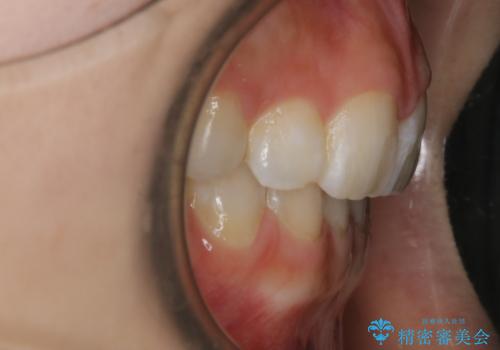

- 歯のガタつきを主訴にご来院されました。

ガタつきがあるだけでなく、元々永久歯が欠損している「先天欠如」で歯の本数が少なく噛み合わせ等も治療する必要がありました。

かなり特殊な状況からの矯正治療になるため抜歯する本数や位置、並んだあとのスペースのコントロールを慎重に計画し、マウスピース装置のインビザラインで治療を開始しました。